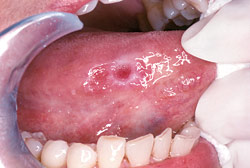

Oral cancer.Most of the lumps, bumps, and occasional sores you find in and around your mouth are completely harmless. But you should look out for changes such as white or red patches, ulcers and lumps anywhere in and around your face and neck that persist for more than a couple of weeks. A persistent sore throat or hoarseness is also cause for concern. Most oral cancers are “squamous” (scale-shaped) cell carcinomas. The sides of the tongue are the most common sites for these small lesions. Because the tongue has a rich blood supply and a direct connection to the lymphatic system (a part of our immune system), it's a site from which cancer can easily spread. The floor of the mouth under the tongue is the second most common site. Cancerous lesions on the lower lip, which are usually preceded by chronic sun exposure, are not uncommon.